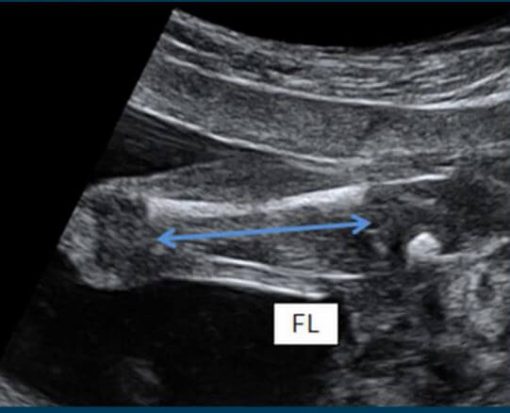

Usg artinya bpd bayi

Usg bpd pengukuran. Baby emir journey: hasil usg dan cara membacanya

Usg keyza familier penjelasan tentunya sepertiku singkatan awam bagi. Usg bpd pengukuran